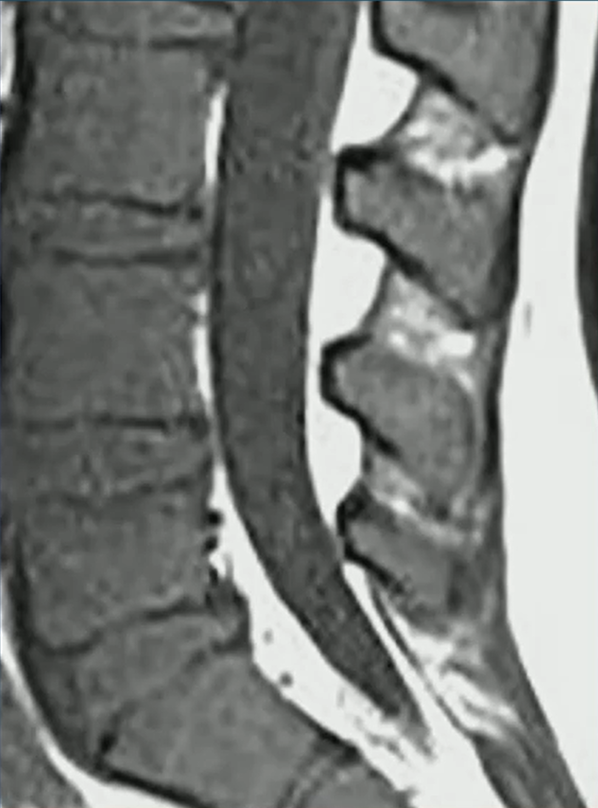

True vs. False Lumen in Acute Aortic Dissection

Look for the beak sign and larger caliber to ID the false; check the arch “wraparound” and calcification patterns for truth.